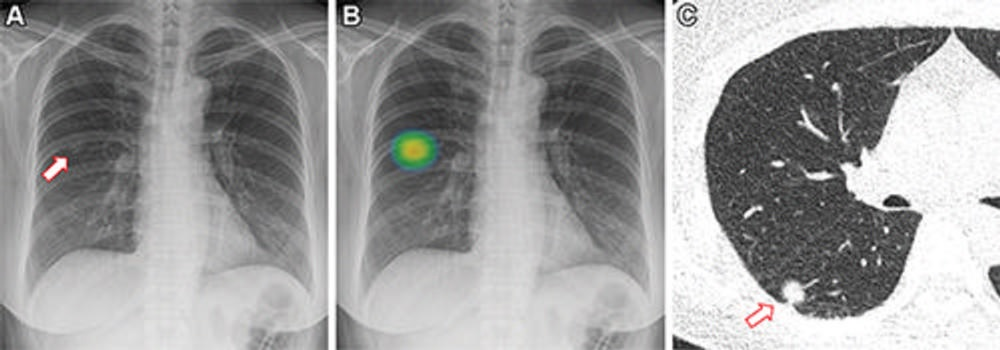

Previously, the group developed an AI chest x-ray model called CAD4COVID and found the model performed comparably to radiologists in triaging suspected COVID-19 cases. The model takes a single frontal chest x-ray as input and produces a score in the range of 0 to 100 indicating the likelihood of COVID-19, as well as outputs a heatmap image to illustrate the regions of abnormality.